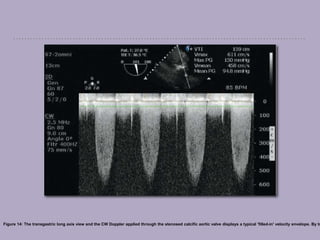

The CWD is displayed as a waveform with a filled-in spectrum caused by the different

velocities being measured along the scan line [Figure 14]. A turbulent flow, caused by

obstruction, results in spectral broadening and increased velocities.

Figure 14: The transgastric long axis view and the CW Doppler applied through the stenosed calcific aortic valve displays a typical 'filled-in' velocity envelope. By tr

Continuous wave Doppler Continuouswave Doppler (CWD) can accurately measure high-velocity flows (<9 m/second) along the beam axis, provided it is parallel to the blood flow. It is used to calculate the grade of stenotic valve lesions and estimates pulmonary artery pressure. [27] Sampling The CWD uses two separate piezoelectric crystals to transmit and receive signals in order to measure all the different blood velocities along the beam axis, continuously. This makes it difficult to accurately know the depth of the reflected signal. The main disadvantage of CWD is its lack of depth discrimination (Range ambiguity). Display The CWD is displayed as a waveform with a filled-in spectrum caused by the different velocities being measured along the scan line [Figure 14]. A turbulent flow, caused by obstruction, results in spectral broadening and increased velocities.

• 96.

Figure 14: Thetransgastric long axis view and the CW Doppler applied through the stenosed calcific aortic valve displays a typical 'filled-in' velocity envelope. By tr